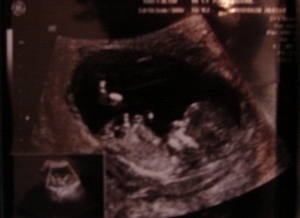

szerdán uh, már számolom vissza a napokat... szerintem én leszek az utcsó, aki a 12. hetire megy... vagy van még, aki utánam megy csak a vizsgálatra?